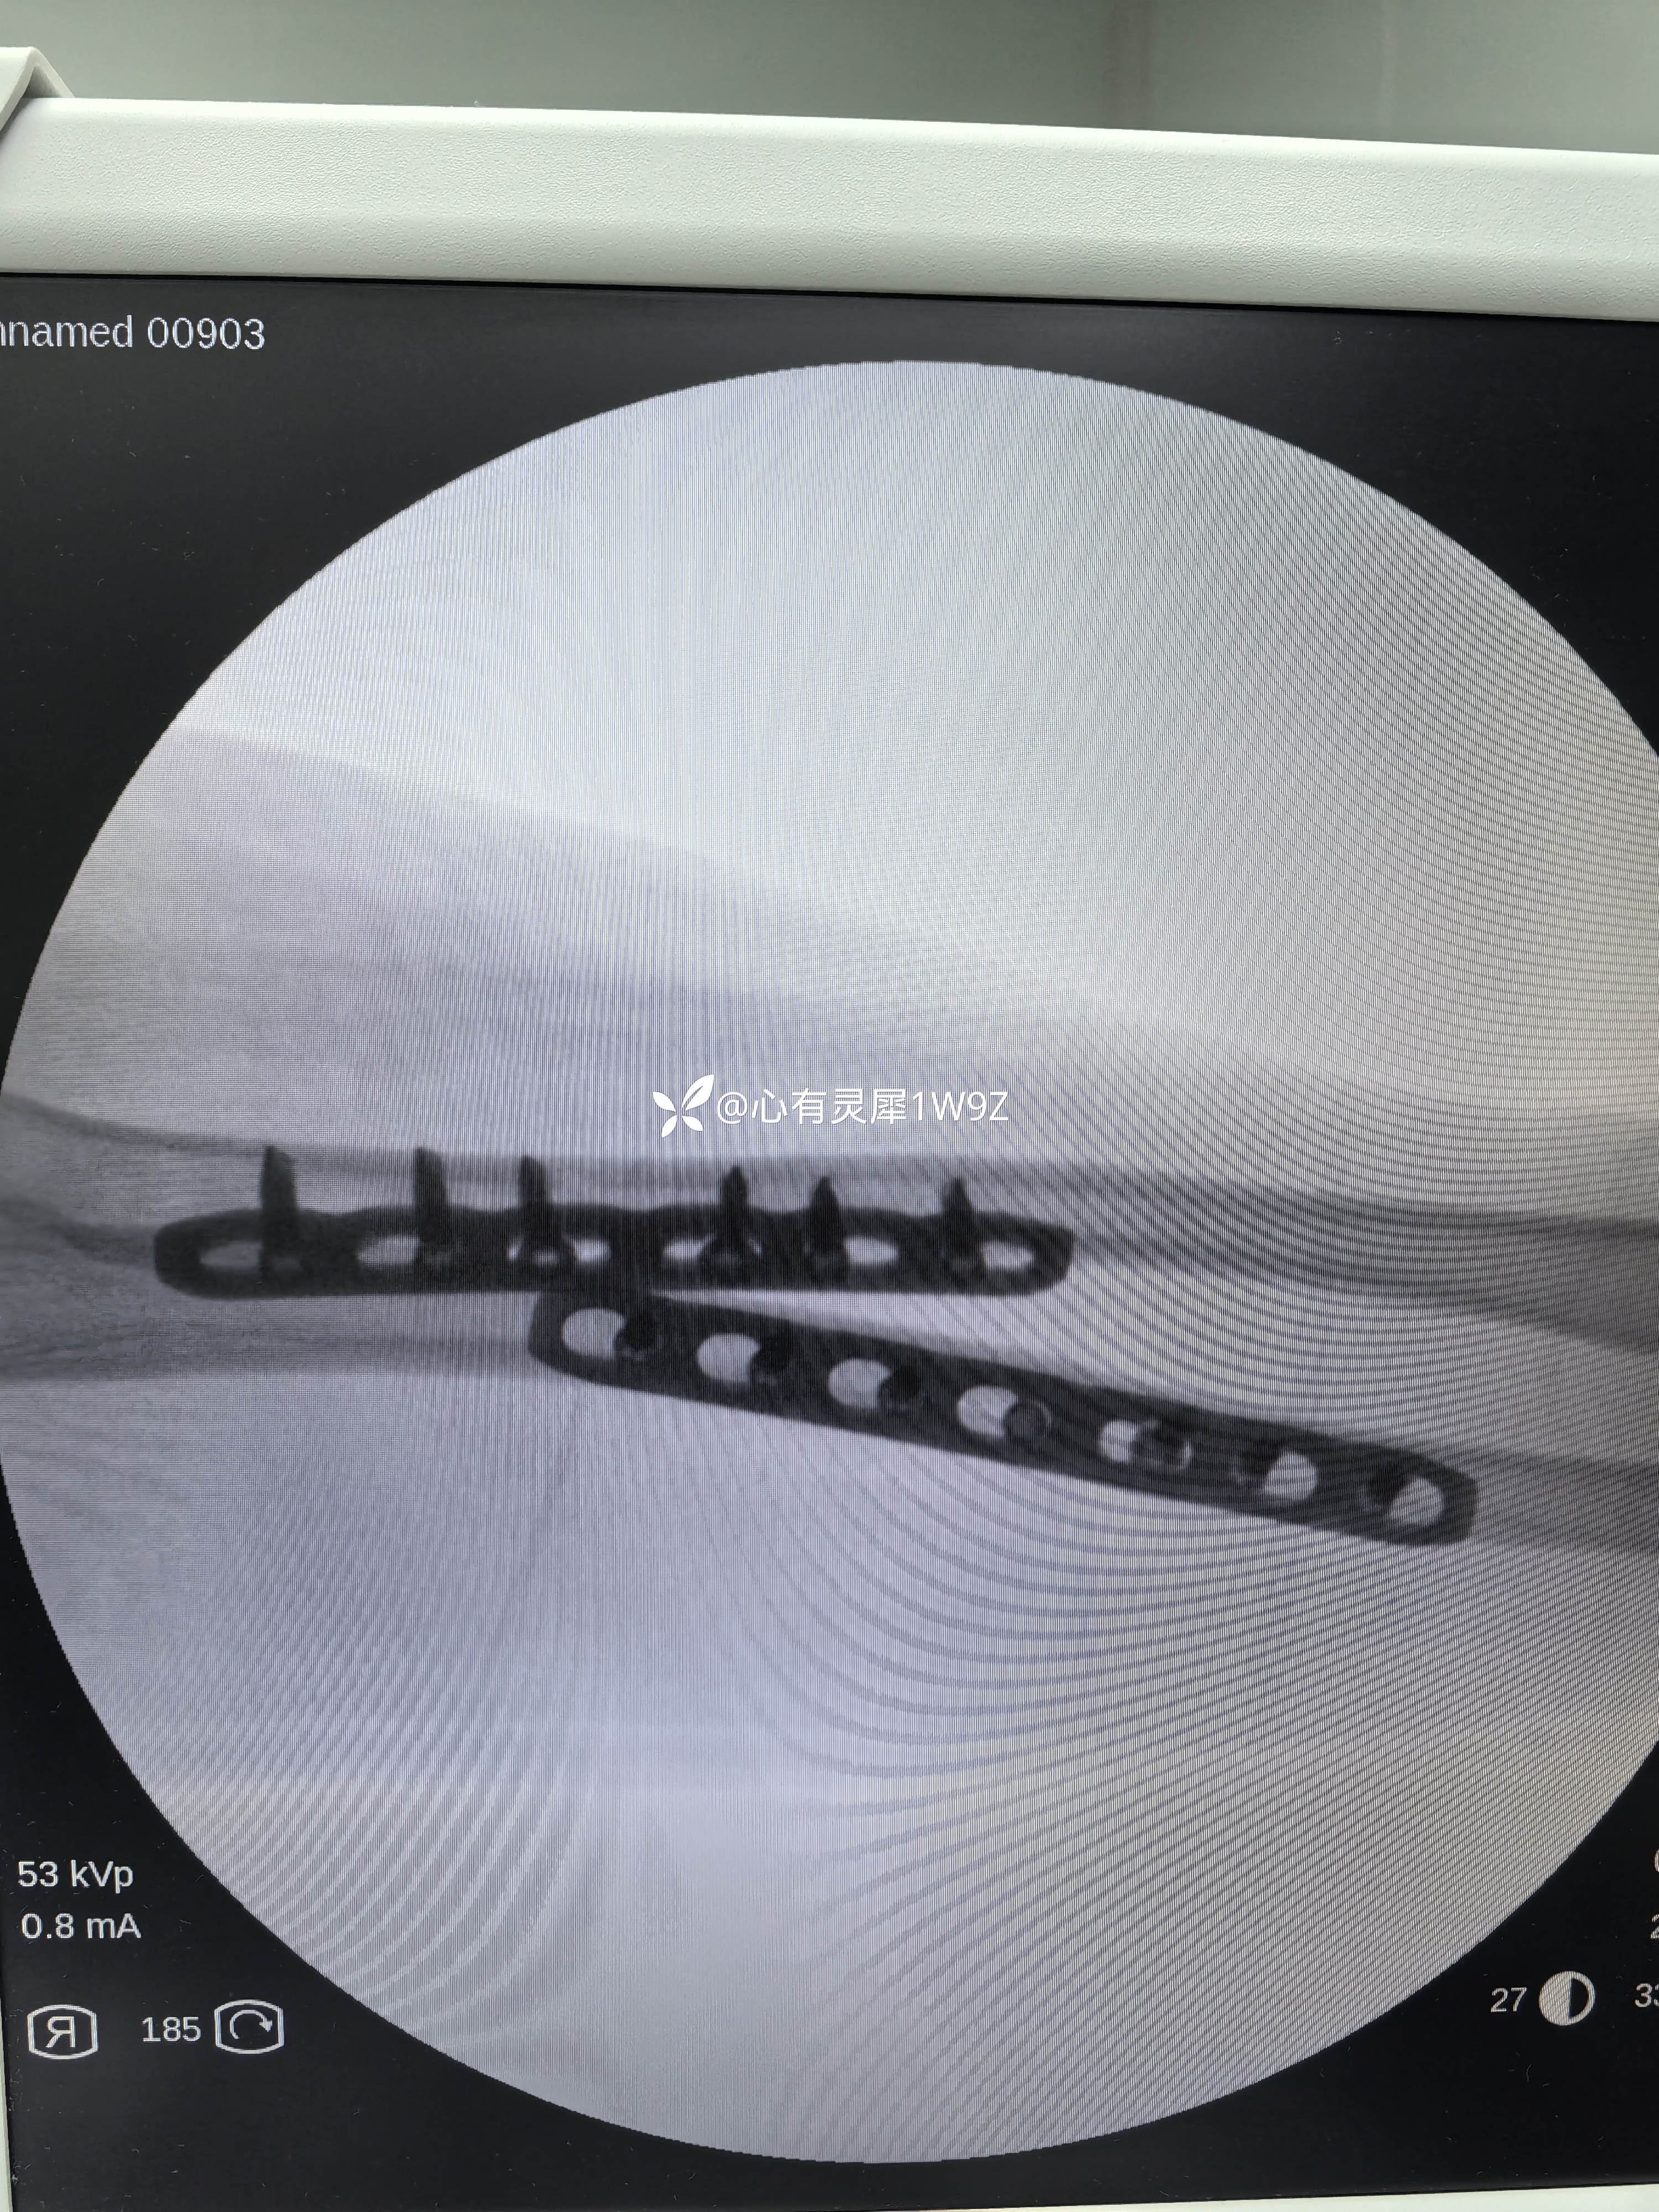

尺桡骨双骨折钢板内固定

【临床诊断】:左侧尺桡骨双骨折

【治疗经过及结果】:臂丛麻醉下切开复位内固定手术。

桡骨近端骨折,手术切口选择一般有背侧入路掌侧入路两种选择。背侧入路需要显露保护桡神经深支,掌侧入路需要保护桡动静脉,结扎桡动脉分支,近端也要小心桡神经深支。各有各的特点,根据自己的经验选择切口。手术中要有耐心,小心显露,不能急躁。